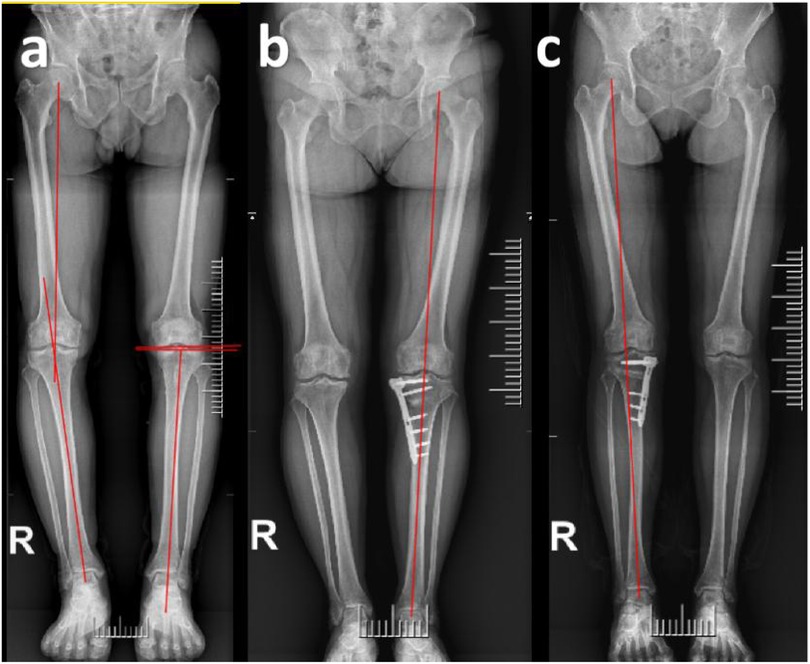

A total of 157 patients who underwent open-wedge high tibial osteotomy (OWHTO) followed by second-look arthroscopy were included as the study cohort. The patients were divided into two groups: the OWHTO with MMPRT repair group (n = 82) and the OWHTO-only group (n = 75). Patients who underwent MMPRT repair using the pull-out technique during OWHTO were assigned to the repair group, while those who only received debridement of the degenerative portion of MMPRT without repair were assigned to the non-repair group. Whether to repair the meniscus is determined based on preoperative imaging observations, intraoperative meniscus tear conditions, and patient preferences. All results were obtained retrospectively from medical records. Additionally, each group was further subdivided into Fujisawa and Neutral subgroups. The patient selection process is illustrated in Figure 1. Postoperative lower limb alignment passing through 60%–65% of the tibial plateau width was classified into the Fujisawa subgroup, while alignment passing through 50%–55% of the tibial plateau width was assigned to the neutral subgroup (4, 5) (Figure 2). The alignment results were obtained from postoperative measurements. Cases where the postoperative alignment did not meet the standards were excluded, and this information is presented in Figure 1.

Figure 2. Radiographic evaluation examples. (a) Schematic diagram for measuring HKA, MPTA and JLCA. The hip-knee-ankle (HKA) angle was defined as the angle between the line from the center of the femoral head to the midpoint between the tibia intercondylar eminences and the line from the midpoint between the tibia intercondylar eminences center to the talus joint surface center. The medial proximal tibial angle (MPTA) was defined as the angle between the mechanical axis of the tibia and the proximal articular surface of the tibia. The joint line convergence angle (JLCA) is defined as the angle formed between the distal femoral articular surface and the proximal tibial articular surface in the coronal plane. (b,c) Postoperative lower limb alignment passing through 50%–55% of the tibial plateau width was classified into the Neutral subgroup, while alignment passing through 60%–65% of the tibial plateau width was assigned to the Fujisawa subgroup.